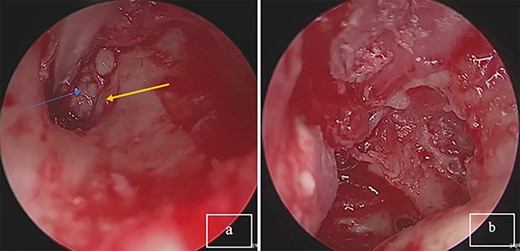

An endoscopic exploratory tympanotomy was performed. During the procedure, we found a bony mass filling the atrium. The bony structure was free from the surrounding walls of the middle ear, it was found that the stapes was absent, and descending branch of the incus was lysed. A polypoidal mass filling the attic. A complete surgical excision of the mass was performed endoscopically (Fig. 2). After the removal of the mass, a tympanoplasty type III was performed using a chondral perichondrial graft from tragus.

(a) Tumor mass in the eardrum, blue arrow: tumor; yellow arrow: corda tympani. (b) Complete resection of the tumor.